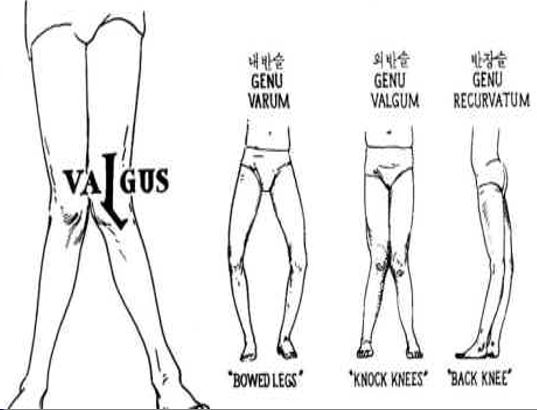

슬관절 변형 종류

슬관절 변형의 종류는 내반슬, 외반슬, 전반슬 등 총 세 가지입니다.

1. 내반슬

- 슬관절이 외측으로 활 모양으로 휘어진 상태

- 경골의 내염전변형 동반

2. 외반슬

- 슬관절이 과도하게 내측으로 휘어져 있는 변형

- 외상으로 인한 골단판의 손상 및 감염, 구루병, 퇴행성 관절염, 류마토이드 관절염 후유증 등이 원인입니다.

- 정면 주시 시 X자형의 다리모양, 슬개골의 외측 아탈구 시 외반슬을 의심해 볼 수 있습니다.

3. 전반슬

- 슬관절이 과도하게 후방으로 휘어져 있는 변형

- 선천성 뇌혈관 이상이 있는 장애아나 외상으로 경골과 대퇴골 골단판 앞쪽 부분의 성장이 지연 등이 전반슬의 원인으로 지목되고 있습니다.

- 측면 주시 시 과도한 Extension의 다리 모양일 때 외반슬이라고 의심해 볼 수 있습니다.